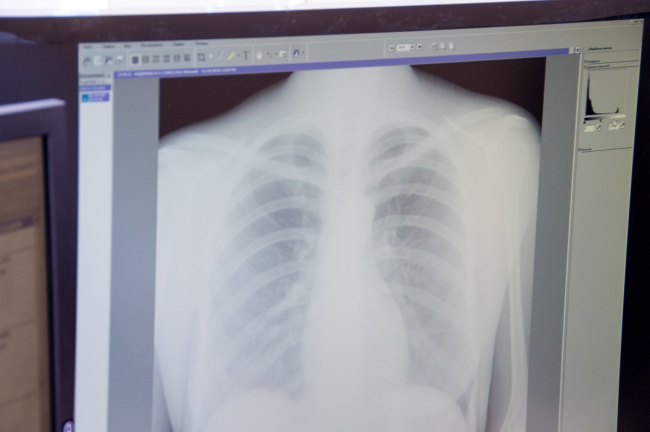

В ПМР ведется работа по профилактике туберкулёза. В первую очередь это массовая флюорография, на реализацию которой нацелены медицинские работники всех специальностей. Каждый врач может направить пациента на флюорографию органов грудной клетки с профилактической целью. Профилактическая флюорография позволяет ежегодно выявлять до 55% всех случаев туберкулёза лёгких. Также проводятся агитационные мероприятия, лекции для учащихся, студентов.

Последние несколько лет флюороохват населения составлял от 80% до 85%, в прошлом году из-за пандемии он значительно снизился и составил 61%. За первое полугодие прошлого года было выявлено 144 случая заболевания, а в первое полугодие 2021 года эта цифра составила 130.